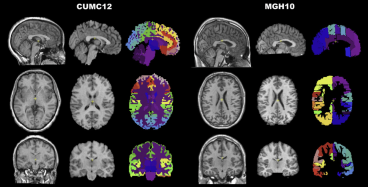

A Klein, SS Ghosh, FS Bao, J Giard, Y Hame, E Stavsky, N Lee, B Rossa, M Reuter, EC Neto, A Keshavan. Mindboggling morphometry of human brains. PLoS Computational Biology 13(3): e1005350 (2017). doi:10.1371/journal.pcbi.1005350

A Klein, J Tourville. 101 labeled brain images and a consistent human cortical labeling protocol. Frontiers in Brain Imaging Methods. 6:171 (2012). doi:10.3389/fnins.2012.00171. Data.